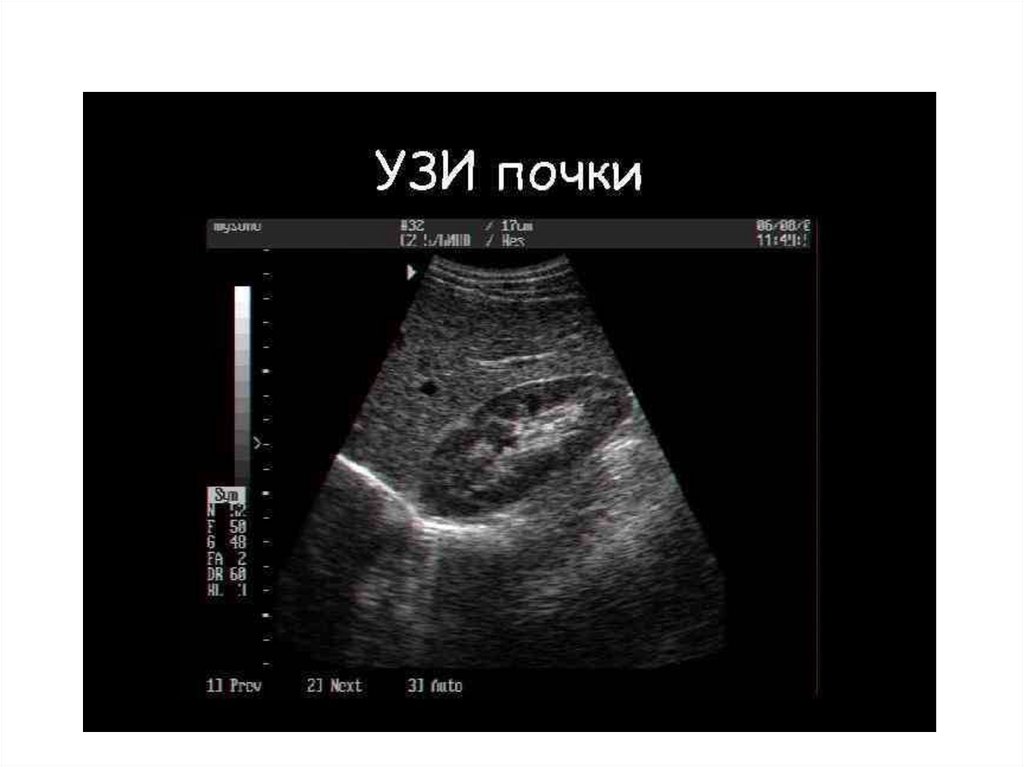

Гидронефротическая трансформация

Расширение чашечно-лоханочной системы почки

Пиелэктазия